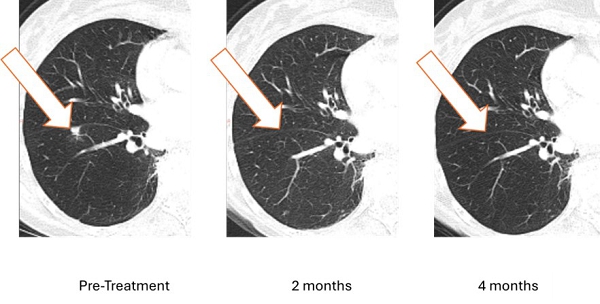

On February 3, 2025, the Company announced an unprecedented clinical response including resolution of a lung metastasis (breast cancer tumor that spread to the lung) with stable disease elsewhere, The patient is the first metastatic breast cancer (MBC) patient treated with Bria-OTS™. Bria-OTS™ is a personalized off-the-shelf immunotherapy, currently under investigation in a Phase 1/2a dose escalation study (ClinicalTrials.gov identifier: NCT06471673) in metastatic recurrent breast cancer. Bria-OTS™ represents a personalized, next generation, advancement of BriaCell’s lead candidate Bria-IMT™ which is currently in a pivotal Phase 3 study for metastatic breast cancer.

On April 24, 2025, BriaCell Confirmed 100% Resolution of Lung Metastasis with Bria-OTS (Figure 1). Complete resolution of lung metastasis confirmed at 4 months follow-up in a hormone receptor positive (HR+) breast cancer patient. Treatment well-tolerated and the patient remained on study with stable disease elsewhere. Sustained clinical response supports Bria-OTS personalized, off-the-shelf immunotherapy approach in Phase 1/2a metastatic breast cancer study.Figure 1: Treatment with Bria-OTS monotherapy resulted in 100% resolution of tumor in the lung of the MBC patient following 2 months of therapy and confirmed at 4 months of therapy1 (axial and coronal views)

1 Note that the other white dots in the lungs are blood vessels.

As shown, the lesion in the patient’s right lung is undetectable after two months and confirmed resolved at 4 months. The updated images supersede those previously reported.